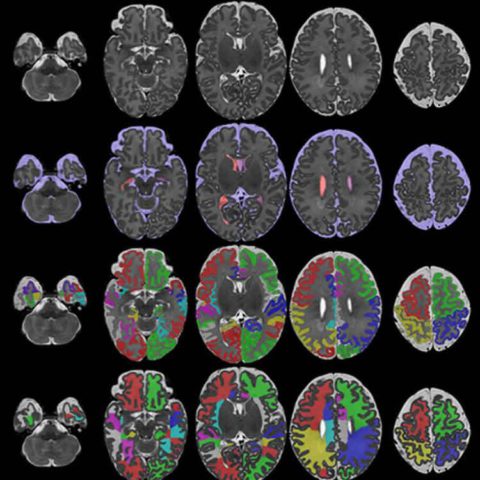

Изучение DMN — это настоящее приключение в мире современных технологий и методов нейровизуализации․ Наиболее распространёнными являются функциональная магнитно-резонансная томография (фМРТ) и позитронно-эмиссионная томография (ПЭТ)․ Эти методы позволяют наблюдать активность различных участков мозга в реальном времени во время выполнения экспериментов․

Также учёные используют методики анализа сети и графовую теорию, что позволяет им понять, как связаны между собой различные области мозга и как эта связность изменяется в зависимости от состояния человека․

| ФМРТ | Отслеживание кровотока в мозге, показывающее активность | Определение активных областей и связей в сети DMN |

| ПЭТ | Использование радиоактивных веществ для изучения функций мозга | Изучение обмена веществ и связей сети |

| Графовые методы | Анализ связей между областями мозга | Понимание структуры сети и её динамики |

Все эти методы дают возможность в деталях рассматривать активность и структуру DMN, что способствует расширению наших знаний о внутренней работе мозга․